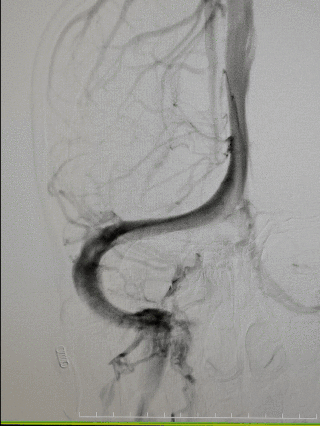

图4右颈内动脉海绵窦段起始部类圆形瘤样扩张,最大约19mm╳14mm,瘤颈约14mm,瘤内射流明显,载瘤动脉远端5mm,近端4.5mm。